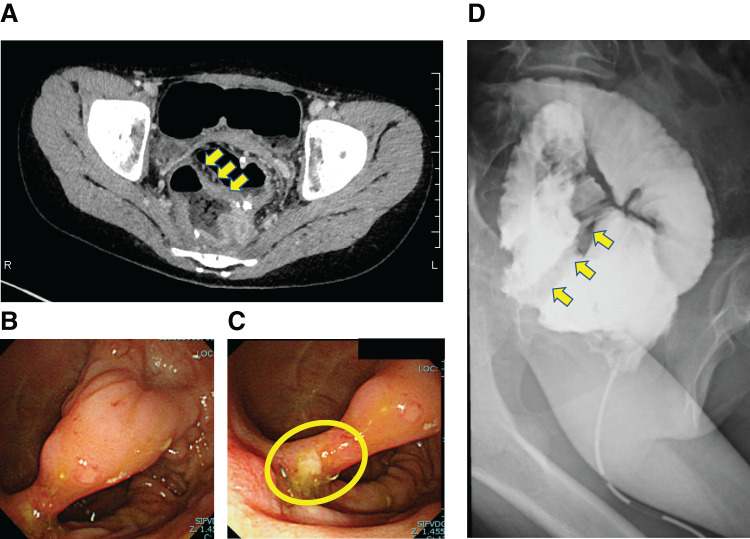

Case presentation: A 12-year-old girl presented to our hospital because of anal pain. She had undergone three-stage surgery for ulcerative colitis refractory to medical therapy, the third stage (stoma closure) having been performed 1 month before the present admission. A computed tomography scan to investigate the possibility of a perianal or pelvic abscess showed no abscess, but revealed what appeared to be a thickening of the wall of the J-pouch, suggestive of pouchitis. Endoscopy revealed a mucosal bridge crossing the anterior and posterior walls of the J-pouch, with a stapler line near the posterior wall's root; however, there was no evidence of pouchitis. While creating the J-pouch (during the second stage of surgery for ulcerative colitis), we had ensured that an apical bridge was eliminated with a linear stapler. Moreover, a contrast enema of the J-pouch during the present admission demonstrated interruption of contrast in the J-pouch. These findings led us to conclude that the mucosal bridge had probably formed postoperatively, after J-pouch creation. The patient underwent endoscopic resection of the mucosal bridge in the J-pouch using an XXS wound retractor transanally. Both ends of the bridge were cut three times with a 5-mm stapler and the bridge was resected. The patient was discharged after surgery, having experienced immediate resolution of anal pain and no complications. Pathological examination of the resected specimen showed that the ileal wall had bent toward the J-pouch lumen with fibrous adherence on the serosal side, indicating that the mucosal bridge had developed unintentionally post-stoma closure. Preoperative computed tomography showed limited pouch expansion, whereas postoperative computed tomography showed sufficient expansion.